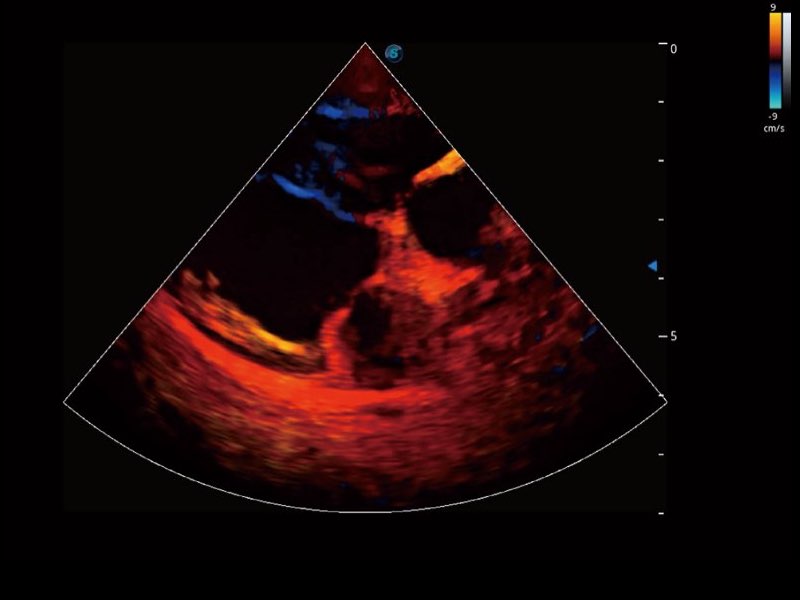

Przy pracach nad aparatem ProPet 60 uwzględniono najważniejsze preferencje i potrzeby weterynarzy, oferując finalnie przystępne cenowo i odpowiednio wyważone połączenie znakomitej precyzji klinicznej, zwiększonej wydajności i przemyślanego przebiegu pracy, niezastąpione w codziennej praktyce weterynaryjnej. Dzięki dostępowi do pełnej gamy głowic HD rozwiązanie to spełnia wszystkie potrzeby w zakresie obrazowania, umożliwiając wykonywanie badań jamy brzusznej, małych narządów, ortopedycznych, badań podczas rozrodu, a nawet badań serca i klatki piersiowej, a to wszystko przy doskonałym stosunku jakości do ceny.